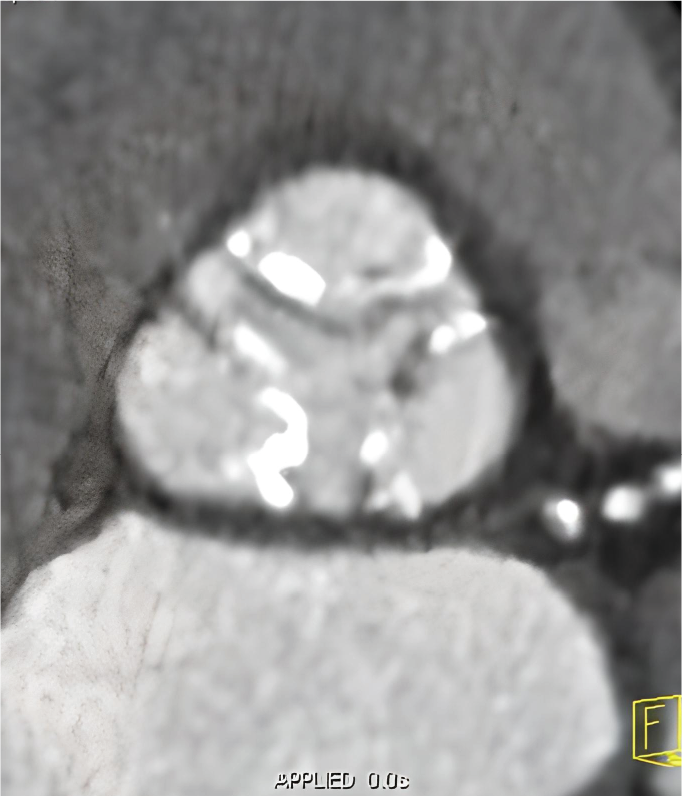

Tomografía cardiaca

Este estudio es adquirido con un tomógrafo de alta velocidad y baja radiación que permite evaluar las arterias coronarias y demostrar la ausencia o la presencia de placas ateromatosas, que son las que ocasionan un infarto (enfermedad arterial coronaria). Mediante la emisión de rayos X es posible obtener imágenes bidimensionales y tridimensionales del exterior y del interior de las arterias coronarias, del corazón y de la función cardiaca.

Una modalidad de la tomografía cardiaca muy utilizada hoy día es el índice de calcio coronario que es útil para identificar oportunamente la presencia de calcio que se asocia con las placas de ateroma que obstruyen tus arterias y ocasionan un infarto. Este estudio se adquiere en menos de un minuto y no se necesita utilizar medio de contraste.

El calcio que se deposita en las arterias coronarias es la “primera señal” que podemos medir antes de que aparezcan los síntomas de la enfermedad y en conjunto con las indicaciones de tu médico, podrás prevenir la progresión de la enfermedad e incluso un infarto.

Cuando es necesario hacer una evaluación mas precisa de tus arterias coronarias la tomografía cardiaca permite, mediante la inyección de contraste por una vena del brazo, estudiar el interior de las arterias y demostrar si existen o no placas que impiden el paso de sangre hacia el corazón, a esta modalidad de la tomografía cardiaca le conocemos como angiotomografía coronaria, que se adquiere en 30 a 60 minutos, y es hoy día el estudio mas confiable para evaluar en forma no invasiva las arterias que nutren al corazón y que cuando se enferman pueden ocasionarte un infarto.

Existen otras indicaciones de la tomografía cardiaca que permiten evaluar las válvulas del corazón y de los grandes vasos como la aorta.